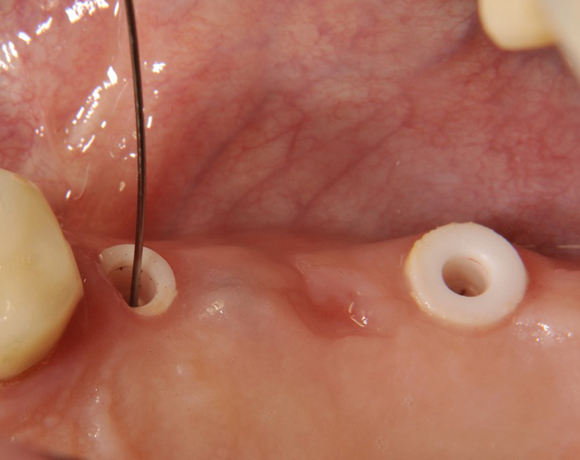

Im vorliegenden Patientenfall wurden für die Zähne 25 und 27 jeweils ein Implantat gesetzt. Nachdem die Implantate eingeheilt waren, wurde 25 – 27 mit einer Brücke versorgt.

Der prothetische Teil